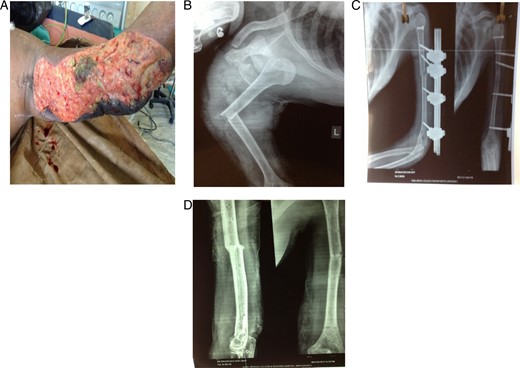

A 30-year-old female came to the emergency department at midnight following a road traffic accident with severe pain and swelling over the left shoulder and arm. Her arm was trapped when the vehicle in which she was travelling skidded off the road. On examination she had degloving injury over posteromedial aspect of the arm extending to axilla with acute bend over arm and loss of shoulder contour (Fig. 1A). Her distal neurovascular structures were intact. Axillary nerve was intact. X-ray (Fig. 1B) showed anterior dislocation with displaced greater tuberosity fracture and transverse fracture of humerus in its middle third. She was managed on next morning. Wound was debrided thoroughly and washed adequately with normal saline. An external fixator was applied on humerus and then shoulder was reduced without difficulty. After reduction, greater tuberosity fracture was found displaced so it was fixed with a cannulated cancellous screw through a deltoid splitting approach (Fig. 1C). Skin grafting over the raw area was done on 10th day after the wound bed was ready. There was poor take over axillary region so another grafting was done after 1 week. After 3 weeks, wound healed completely and then, passive movement at shoulder joint was started. After two and half months, the external fixator was removed and functional brace was applied. After 4 months, the fracture had united completely (Fig. 1D) and brace was discontinued. She had a useful range of motion at the time of brace removal, with abduction and flexion of around 90°. External rotation was ∼20° while internal rotation was normal. At the last follow-up of 11 months, she had a good range of motion with abduction and flexion of 160°flexion and full rotation.

(A) Clinical picture at the time of presentation to emergency. (B) Preoperative X-ray of left shoulder with arm anteroposterior view showing dislocation of shoulder, greater tuberosity fracture and humerus mid-shaft fracture. (C) Postoperative X-ray showing shoulder reduction, greater tuberosity fracture fixation with a cannnulated screw and humerus fracture fixed with external fixation. (D) Four months postoperative X-ray showing fracture union.